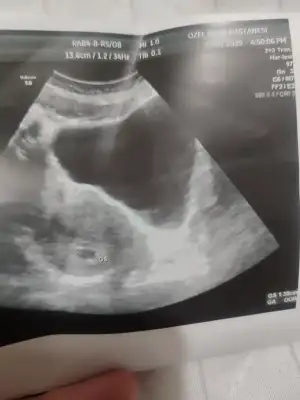

Ben dayanamadım kontrole 6+1 de erken gittim bebeği göremedik haftaya gel dedi doktorum cok erken gelmişsin dedi içim rahat etmedi başka hastaneye de gittim aynı gün onda da görünmedi onun ultrasonu dahada kötüydü onunkine kötü derken 1inde kese 2.45 iken diğerinde 1.30 çıktı hangisine inanayım 😅 haftaya salı gidicem tekrar 7+2 olucam inşallah ozaman görürüm erken gitmemek lazımmış şimdi günler geçmiyor tedirgin bekliyorum oğlumda adet gecikmemin 34. Günü 6+5 te görmüştüm cok minikti kalp atısını 7+5 te duymuştum bunu hiç hesaplamadan gittim hata ettim adet gecikmemin daha 27.günü 6+1 cok erken bir haftaymıs onunla kıyaslasam gitmezdim hic erkenden neyse olan oldu şimdi sabırla bekleyeceğim 🥴😮‍💨

Kızlar selam, 2 hafta önce keseyi görmüştük, bu gün doktora gittik bebişi gördük, kalp atışını da duyduk :KK200: kan ve idrar tahlillerimi verdim, sonuç bekliyoruz.

Son adet tarihime göre 7+1 ama doktor 6+5 ile uyumlu dedi, yumurtlama geç olmuştur dimi, olumsuz bir durum değildir, 2-3 günlük fark?